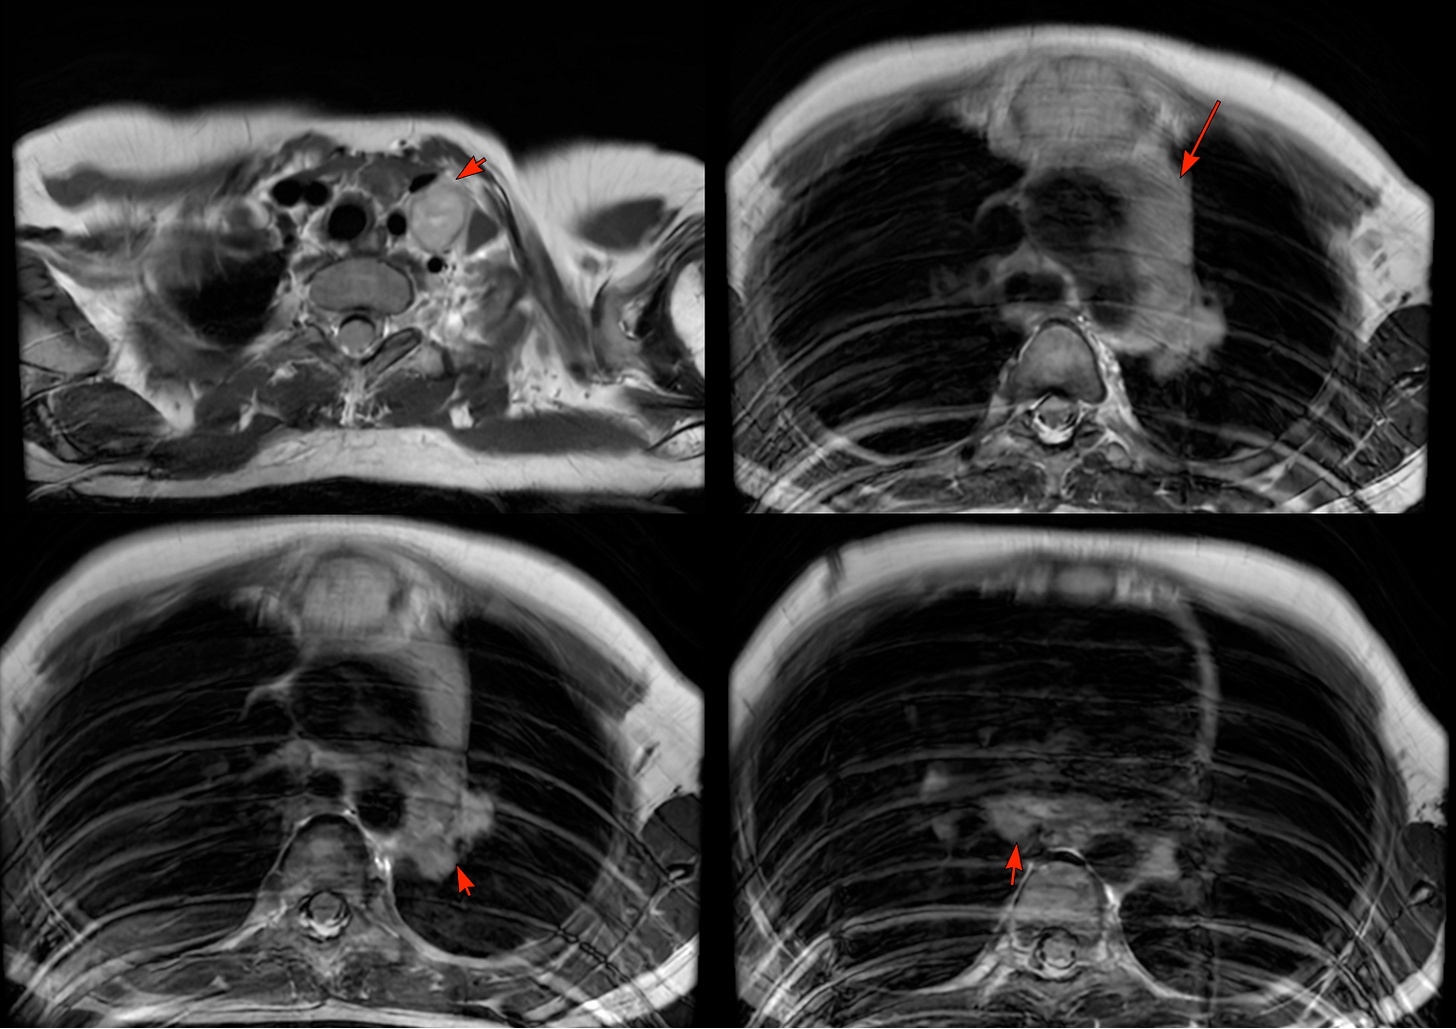

MRI showed an expansile osteolytic lesion in the manubrium sternum.

There were also enlarged left supraclavicular and mediastinal nodes.

The patient was referred for a CT guided biopsy. On CT, the lesion had a “bone-in-bone” appearance.

The video describes the case, the “ballooned-out” manubrium, the concept of spina ventosa, pictures from the 18th century showing spina ventosa in different bones of the body including the craniofacial skeleton and images of different bones show spina ventosa.